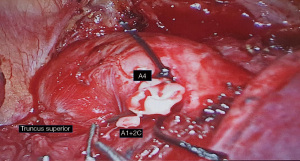

Recognition of this aberrant origin during left VATS upper lobectomy is important as it could be mistaken for mediastinal lingula type and be injured or accidentally ligated. This is especially if the interlobar A4+5 is very small as was in this case. In retrospect what was thought to be the unusually large A1+2c posterior branch was probably a common trunk origin of A4 lingula branch with an adjacent smaller A1+2c branch (Figures 2,3). Such intraoperative complication can be avoided by detailed preoperative study for possible bronchovascular anatomical variations by simulated 3-dimensional multidetector contrast enhanced computer tomography (6,7). This should be supplemented further by meticulous intraoperative dissection and careful identification of mediastinal and interlobar vessels distally into the respective segments before ligation.